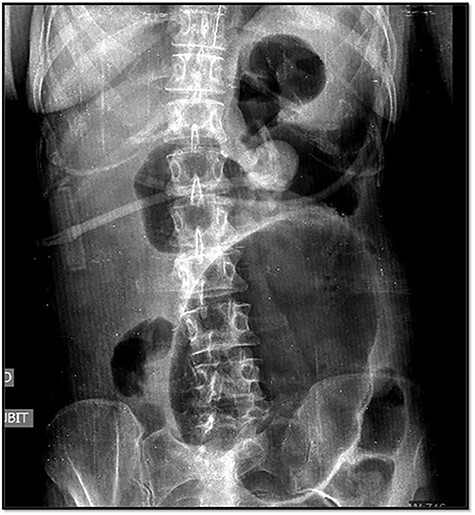

The emergency blood test showed a normochromic and normocytic anemia with an hemoglobin of 10.1 mg/dl and a leukocytosis of 11.150/ul with 70% neutrophils. The abdominal radiography showed a prominent dilation of a small bowel loop. The CT scan reported an 18-cm dilated loop. The main diagnostic suspicion was a small bowel volvulus without signs of ischemia or perforation (Figs 1–3).

In the abdominal X-ray, one of the three typical signs can be observed: dilation of the cecum, a single air-fluid level in the upper left quadrant of the abdomen or the absence of gas in the colon.

However, abdominal radiographs and soluble contrasts have been relegated in favor of computed tomography. This image has a sensitivity close to 100% and a specificity of 90%. Furthermore, it allows the observation of indirect signs of complications such as necrosis or perforation [3].